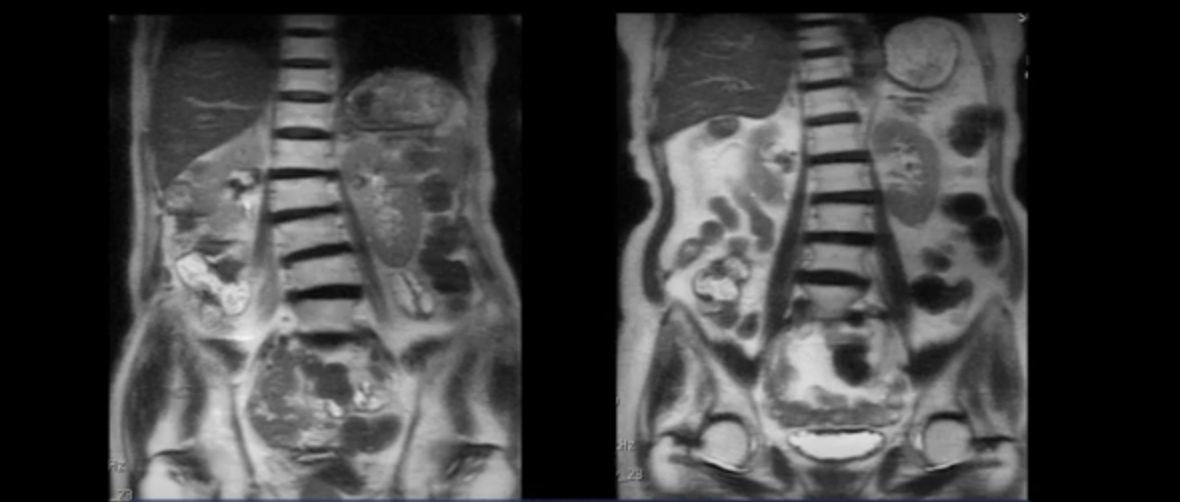

이렇게 근육에 문제가 있다는 걸 가장 쉽게 확인할 수 있는 것이 70대 이상의 협착증 환자의 척추를 보면 거의 전부 다 예외 없이 다 틀어지고 심하게 휘어있습니다. 척추를 반듯하게 잡아주는 게 근육인데, 이 근육이 줄어들고 약해지고 망가지니까 척추가 반듯하지 않고 다 틀어져있는 겁니다. 이 협착증 환자분들은 40, 50대의 비교적 젊은 나이임에도 척추가 다 틀어져있는 게 보이실 겁니다.